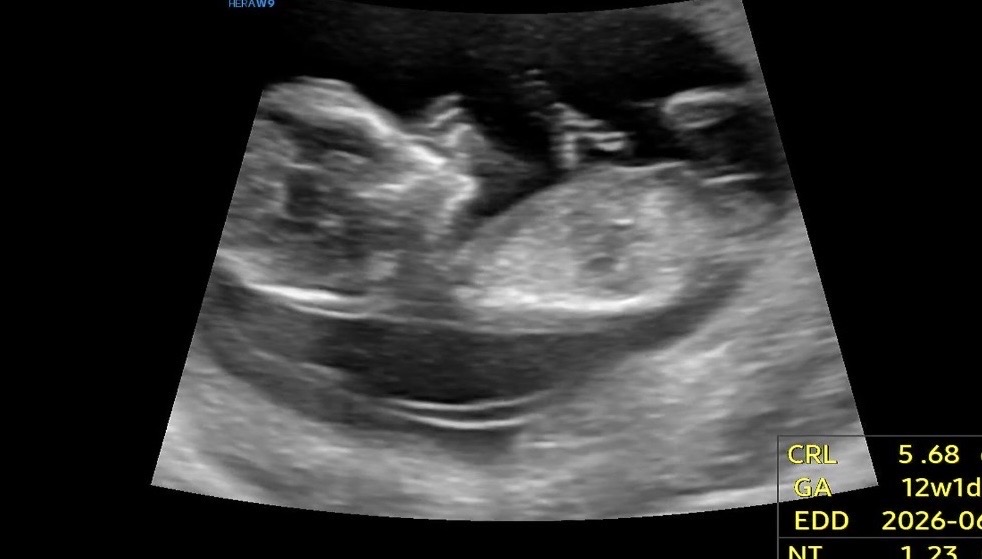

12주차 3일 각도 봐주실 수 있나요 !!?

처음 와준 아기라 그런지 궁금한 것도 많고 설레기도 너무 설레요 !! 🖤 혹시 각도법 봐주실 수 있을까아요 ~?